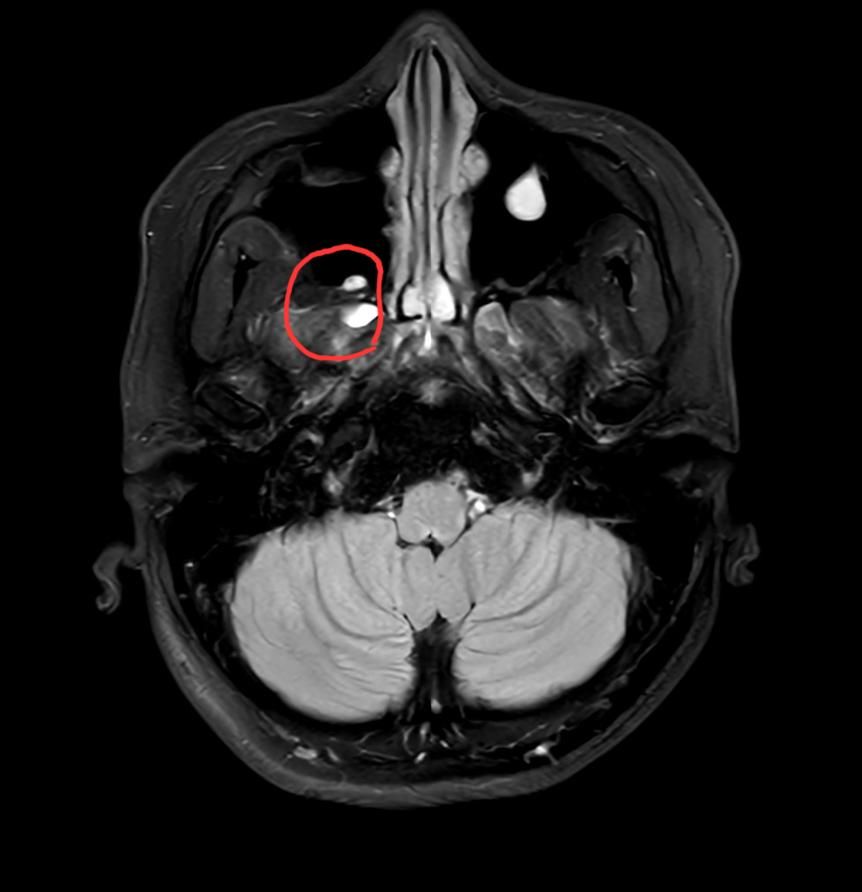

뇌mri 및 ct상 사진 봐주세요ㅠㅠ

한쪽 부비동에 혹부리처럼 물혹이 있는 것은 알고 있었는데 빨간 동그라미 친 부분의 흰색(or덩어리)는 무엇인지 알 수 있을까요?! 처음 보아서 궁금해서요.